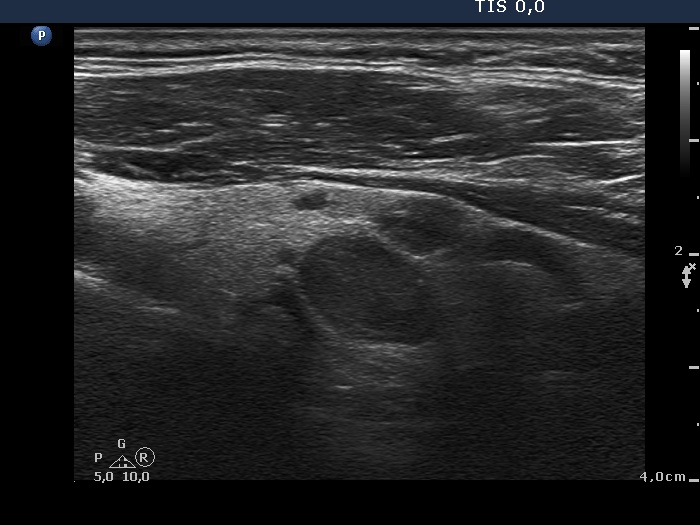

Ultrasonography. The right thyroid was composed of multiple discrete lesions with different echogenicities. The lobe was extremely enlarged with the dimension of 55x65 xminimum 120 mm (width, depth, and length, respectively) and spread retotracheal and substernal. The lower pole of the lobe could not be visualized while swallowing. The left thyroid was normal-sized and contained several hypoechogenic lesions. There was a moderately hypoechogenic nodule in the right lobe. The lesion presented neither halo nor perinodular blood flow.